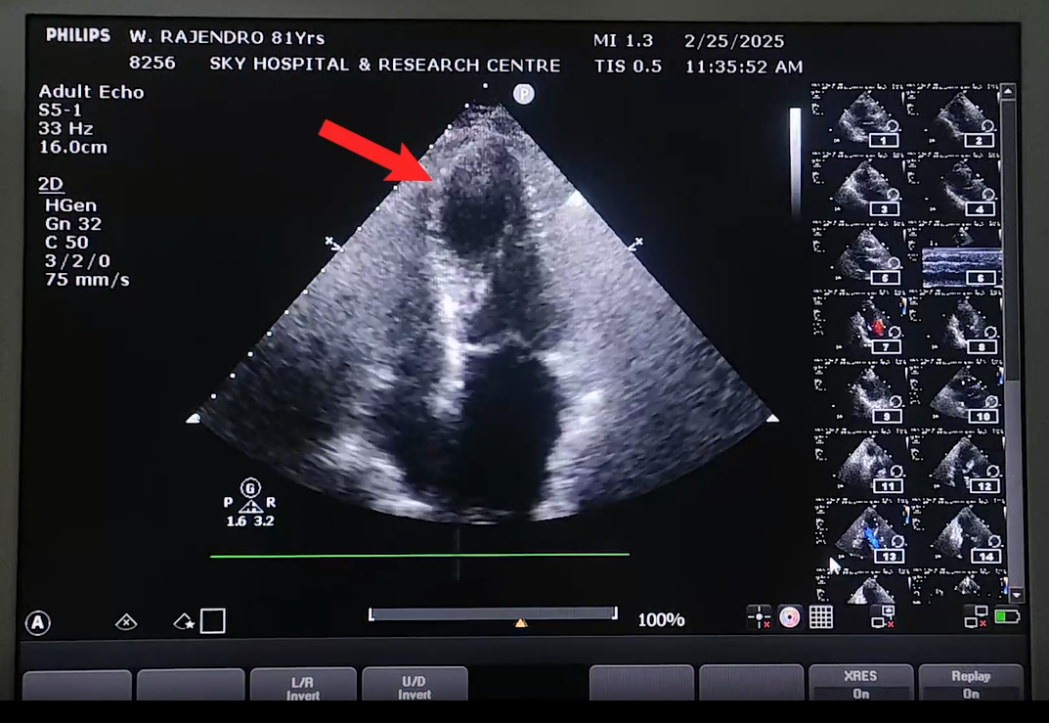

A simultaneously done bedside echocardiogram revealed severe transmural wall motion abnormality in the LAD territory (Figure- 2a, the Echo video).

Figure 2(a): Echocardiogram performed at the time of presentation showing severe transmural wall motion abnormality in LAD territory (marked by an arrow head) with reduced LVEF (45%).

The echocardiogram also showed reduced left ventricular ejection fraction (LVEF) at 45%, moderate mitral regurgitation, mild aortic regurgitation, minimal tricuspid regurgitation, no pulmonary arterial hypertension and normal pericardium. Based on the symptom of ischemic chest pain, findings on ECG of hyperacute T-waves and severe transmural wall motion abnormality on bedside echocardiogram, immediately available pharmacological reperfusion regime consisting of dual antiplatelet drugs with intravenous tenecteplase and subcutaneous enoxaparin were administered to him immediately [10]. Intravenous bolus dose of enoxaparin was omitted considering his age of 81years. His chest pain subsided within minutes of the CDT. Post-lysis ECG showed near normalization of T-wave changes, ST-segment remaining in iso-electric line (Figure 1b). The troponin T test done on presentation came back as normal although the treatment as for ATMI was already started before the result was available. The troponin T done 4 hours later has shown to be grossly elevated at 2000 ng/L. Further investigation revealed that he had dyslipidemia, hyperuricemia and thrombocytopenia (1,18,000/µl).